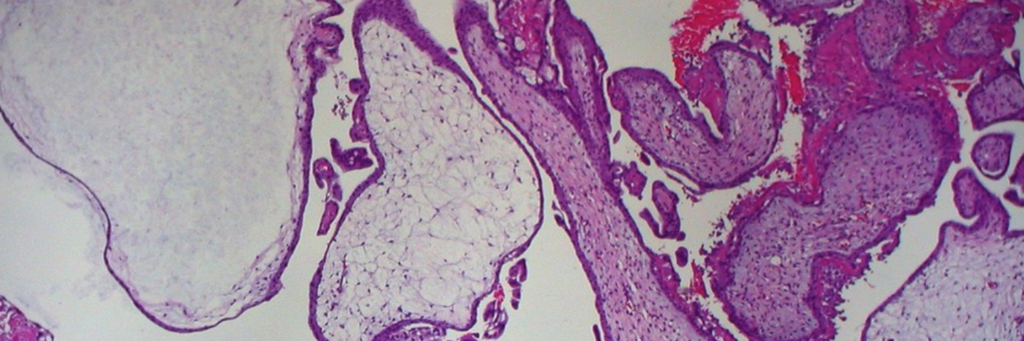

Welcome to the Miami Project Human Spinal Cord Collection